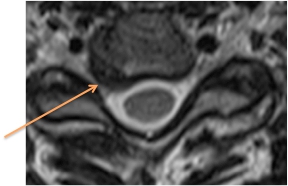

Figure 4. Déplacement anormal d'un disque intervertébral situé au niveau du cou et compression d’une racine nerveuse participant à l’innervation du bras.

Une IRM permet d'évaluer le degré de dégénérescence discale, la présence d'une hernie discale (Figure 4) et l'inflammation des plateaux vertébraux. L'IRM permet d'évaluer l'état de la moelle épinière et notamment la présence d'un signal anormal en cas de myélopathie.